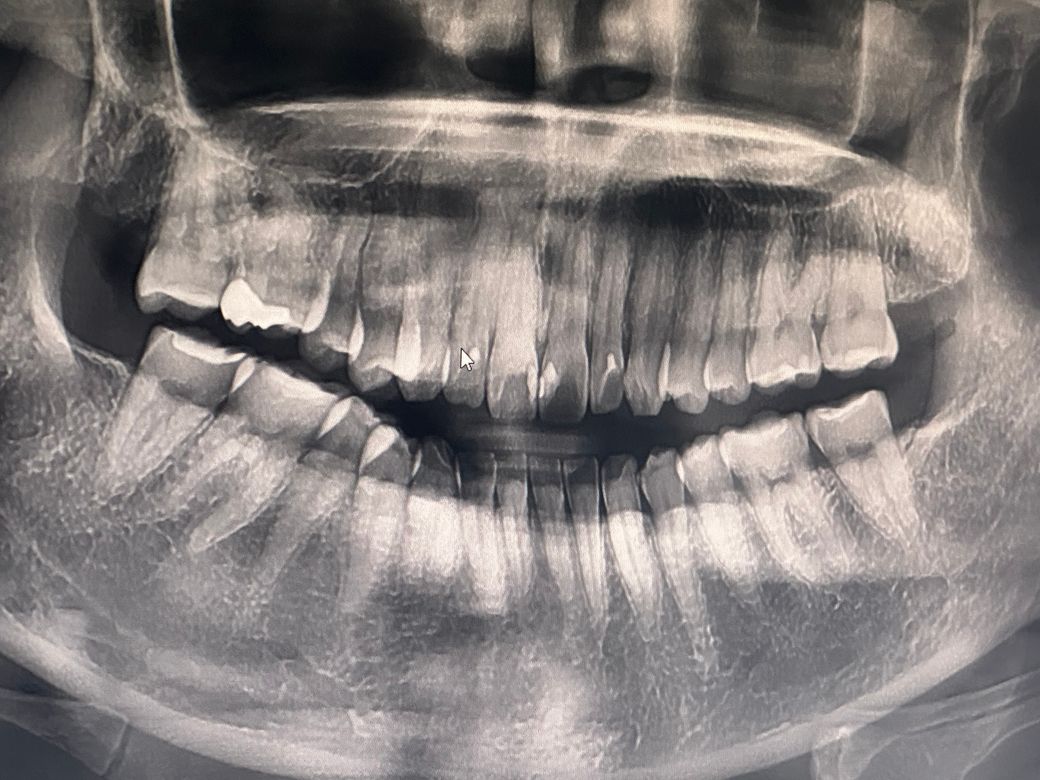

오늘찍은 사진인데 사진상 충치가 있나요?

오늘 찍은 사진입니다

작년 9월에 갔을땐 충치가 없다 들었는데

오늘은 충치에 대해서 딱히 말을 안해주시더라구요

사진상으로는 크게 충치가 보이진 않지만 사진상으로 오른쪽 아래 뒤쪽 치아 사이에 약간 충치가 의심되긴하니 작은 사진을 찍어보시고 확인을 받아보시는게 좋을것같습니다.

눈에 당장 띄이는 것은 없어보입니다. 충치는 언제 생길지 모르니 정기 검진 받으시면 됩니다.

사진으로는 정확한 확인이 어려워 보입니다. 자세한 확인을 위해서 치과에서 진료를 받아 보세요.

큰 파노라마 사진으로는 아주 세세한 충치 확인은 어렵습니다 큰 층치는 없어보이나 시리거나 불편한 증상이 평소 나타난다면 치과 검진 가보시고 작은 엑스레이 사진을 찍어봐야 합니다